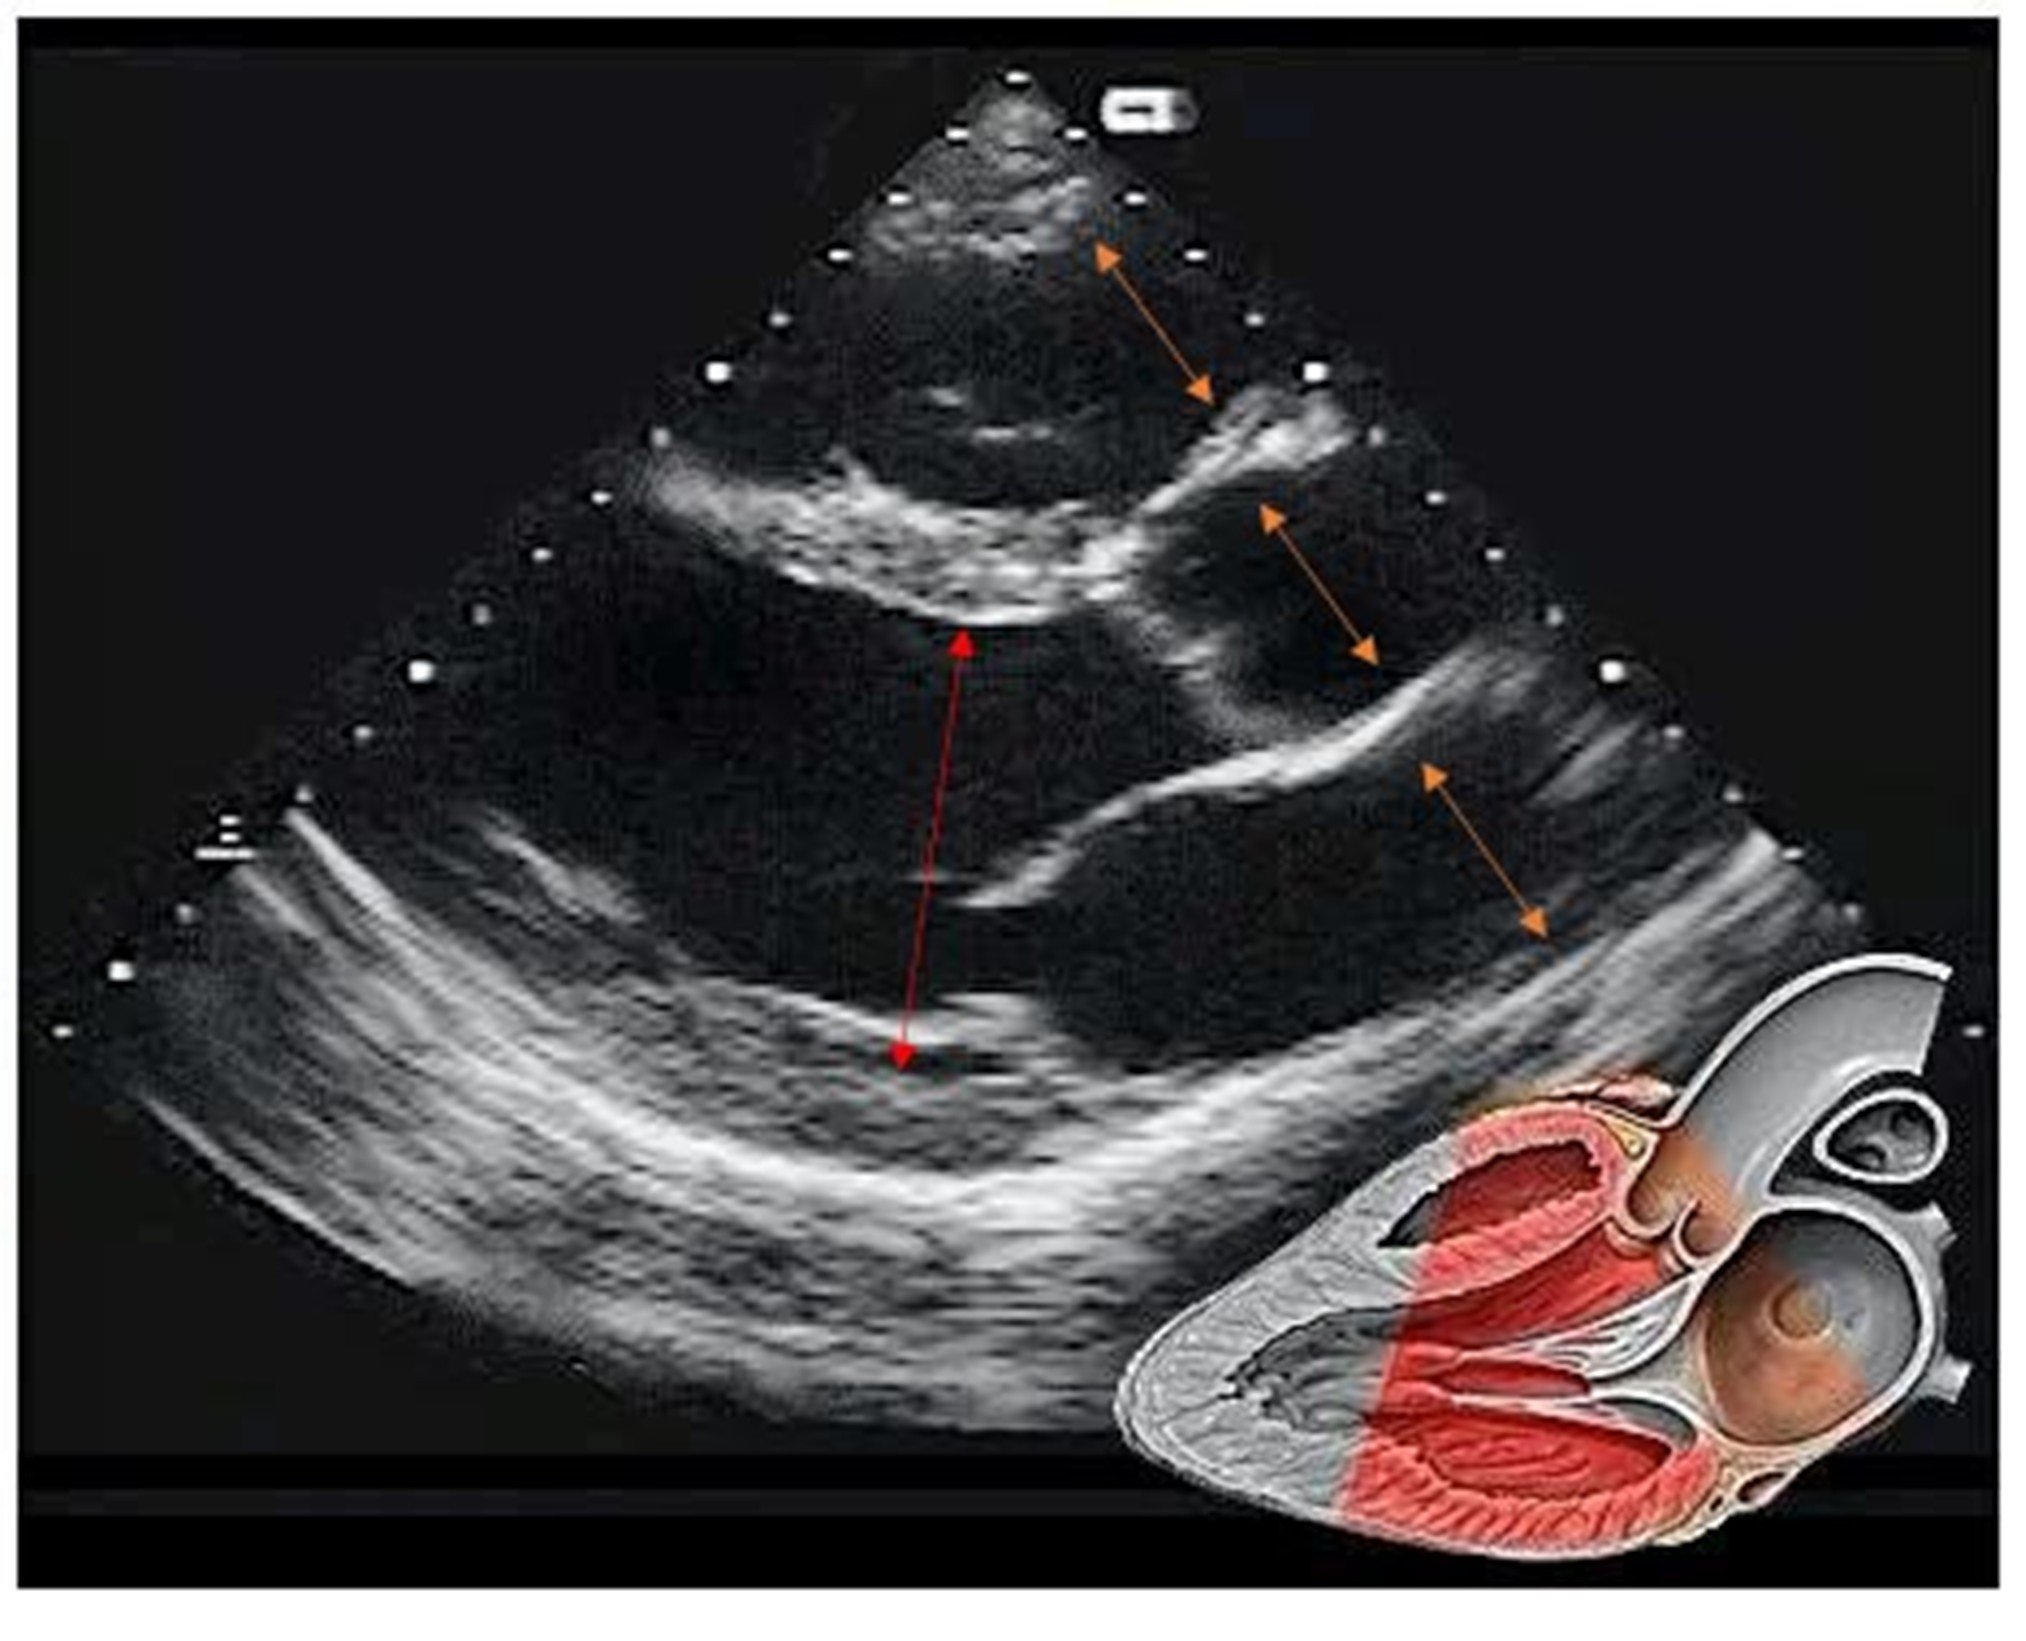

• In the parasternal long axis view the RV-AORTA-LA should be approximately same dimension (ORANGE ARROWS)

• Comparison of the relative dimensions can indicated abnormalities in one or more of these structures

• The LV cavity (internal dimension) measure in end diastole (largest diameter in the cycle) can provide detail on LV dilation and size this can be done by gross comparison to the depth markers on the side of the image (white dash line - usually 1 cm increments)

• Males > 5.8 cm and females > 5.2 cm considered dilated - anything measuring 6cm or more suggests a dilated LV